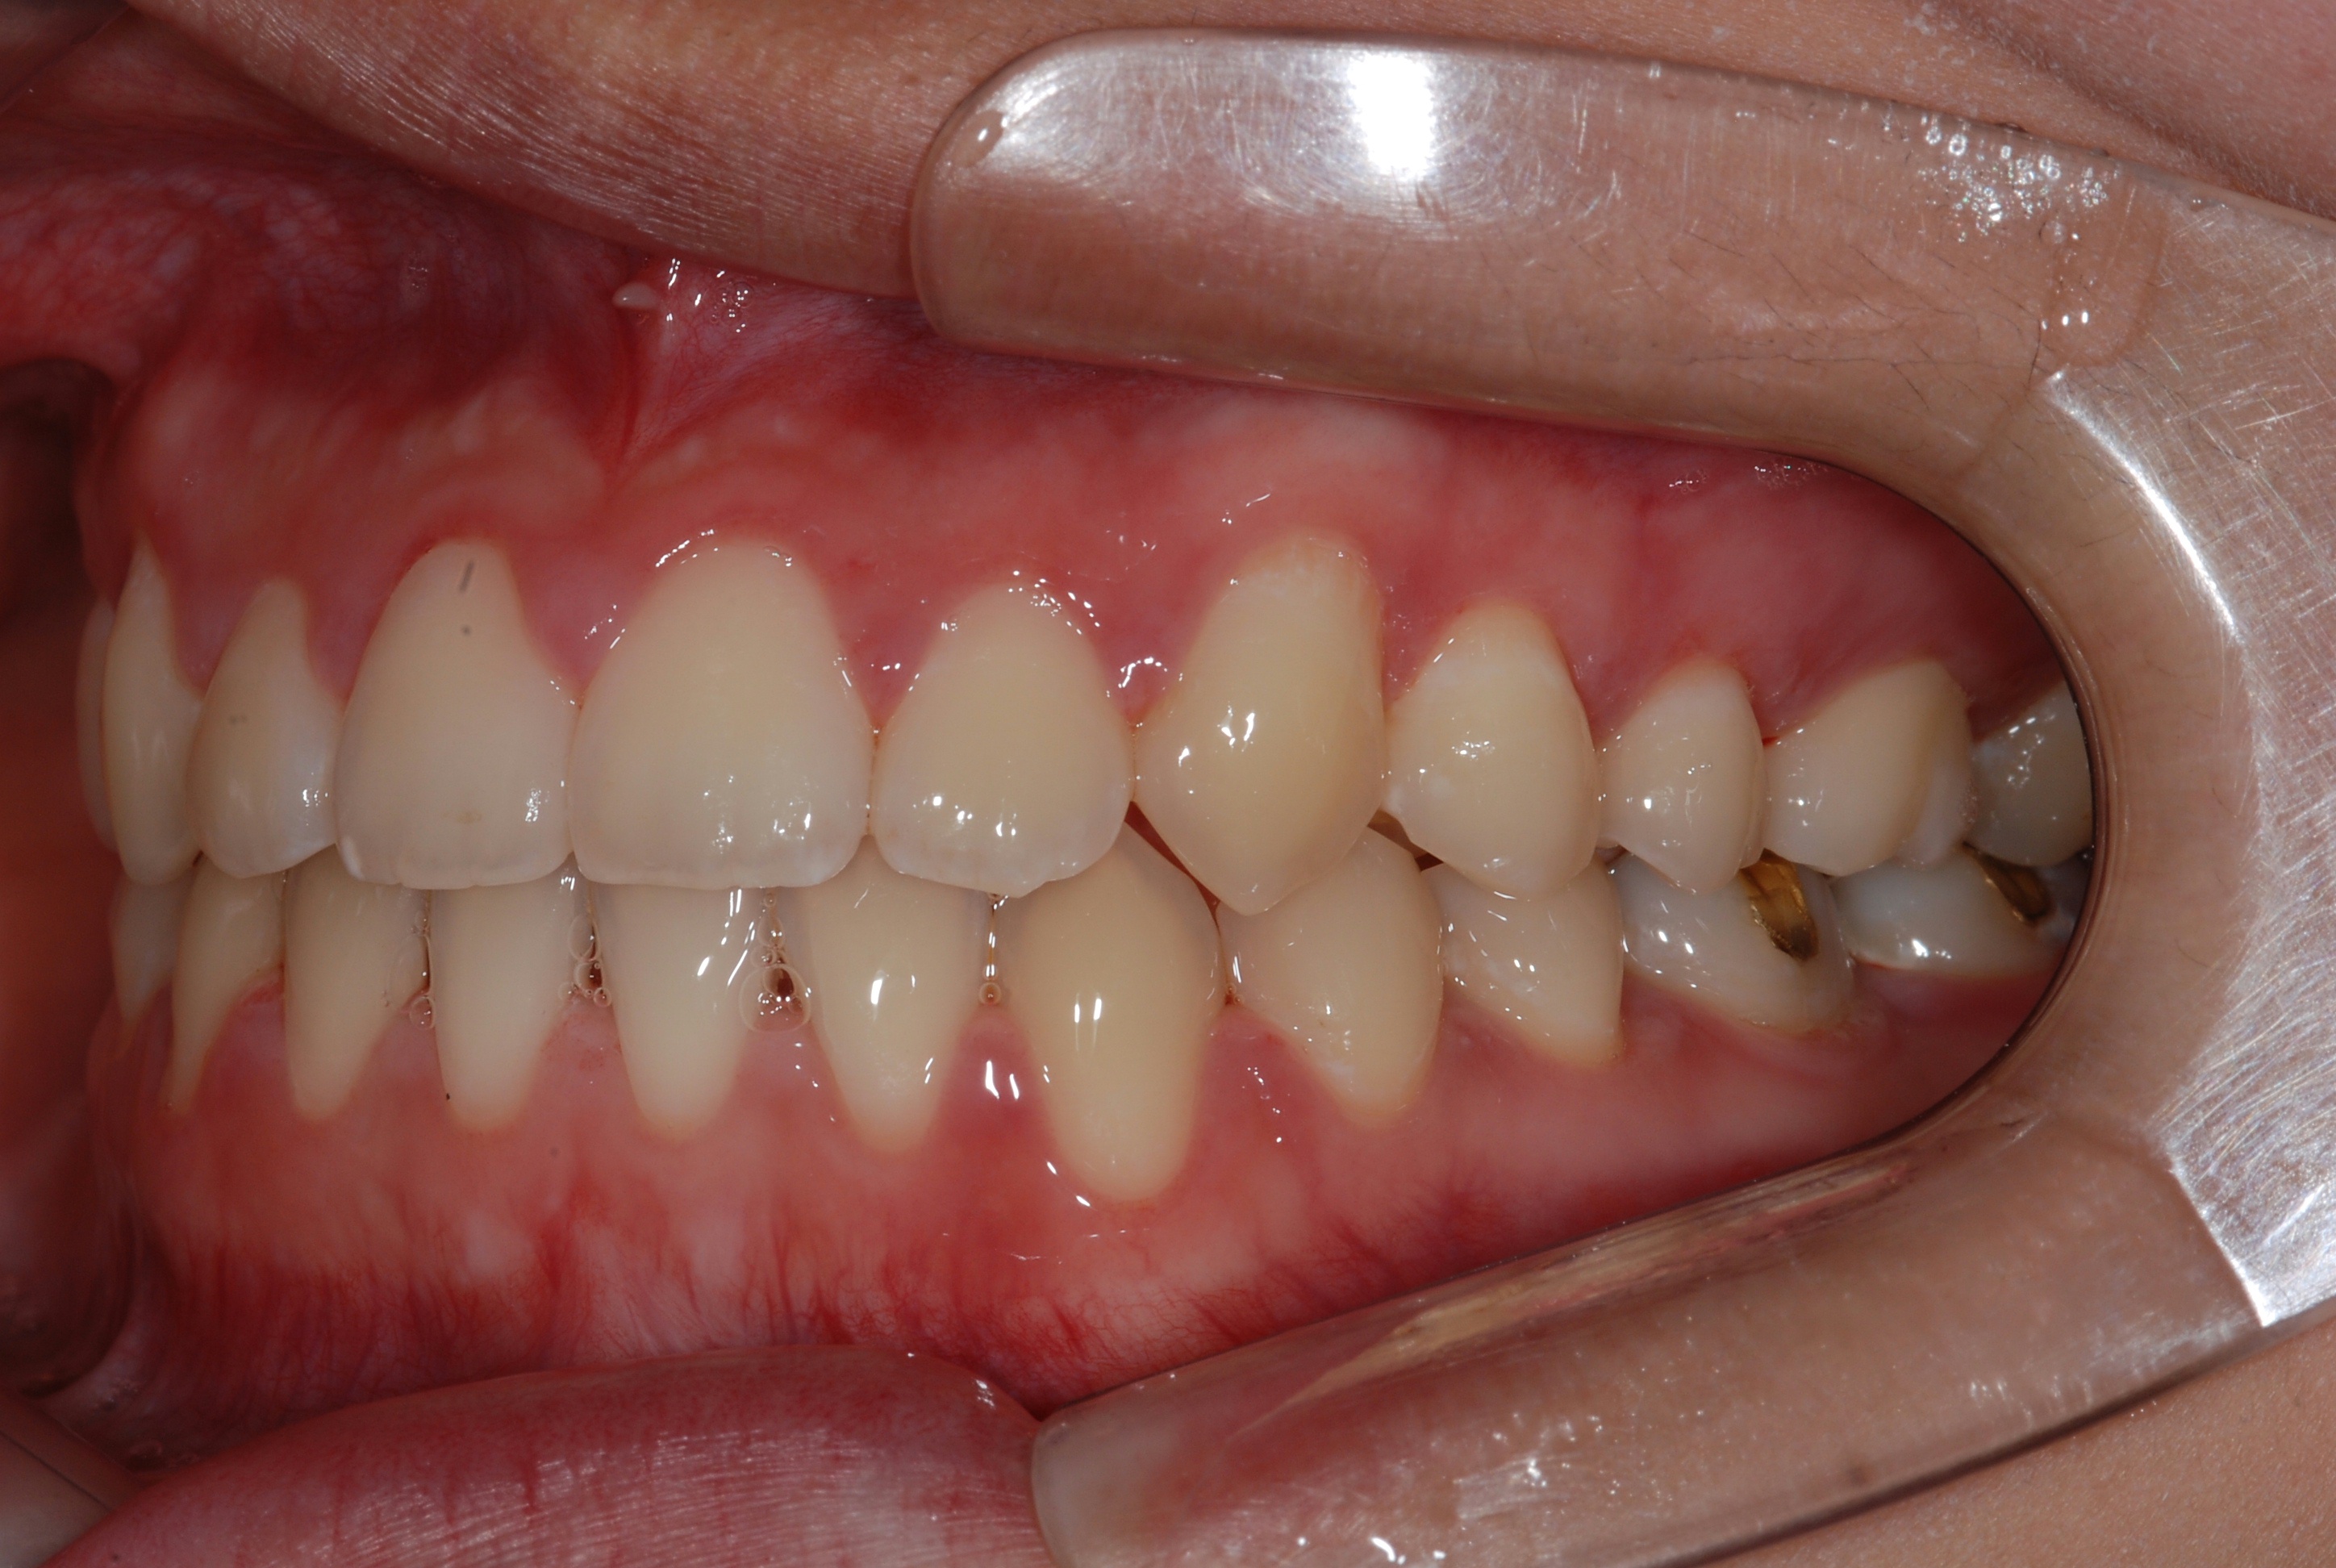

치료 후 사진입니다.